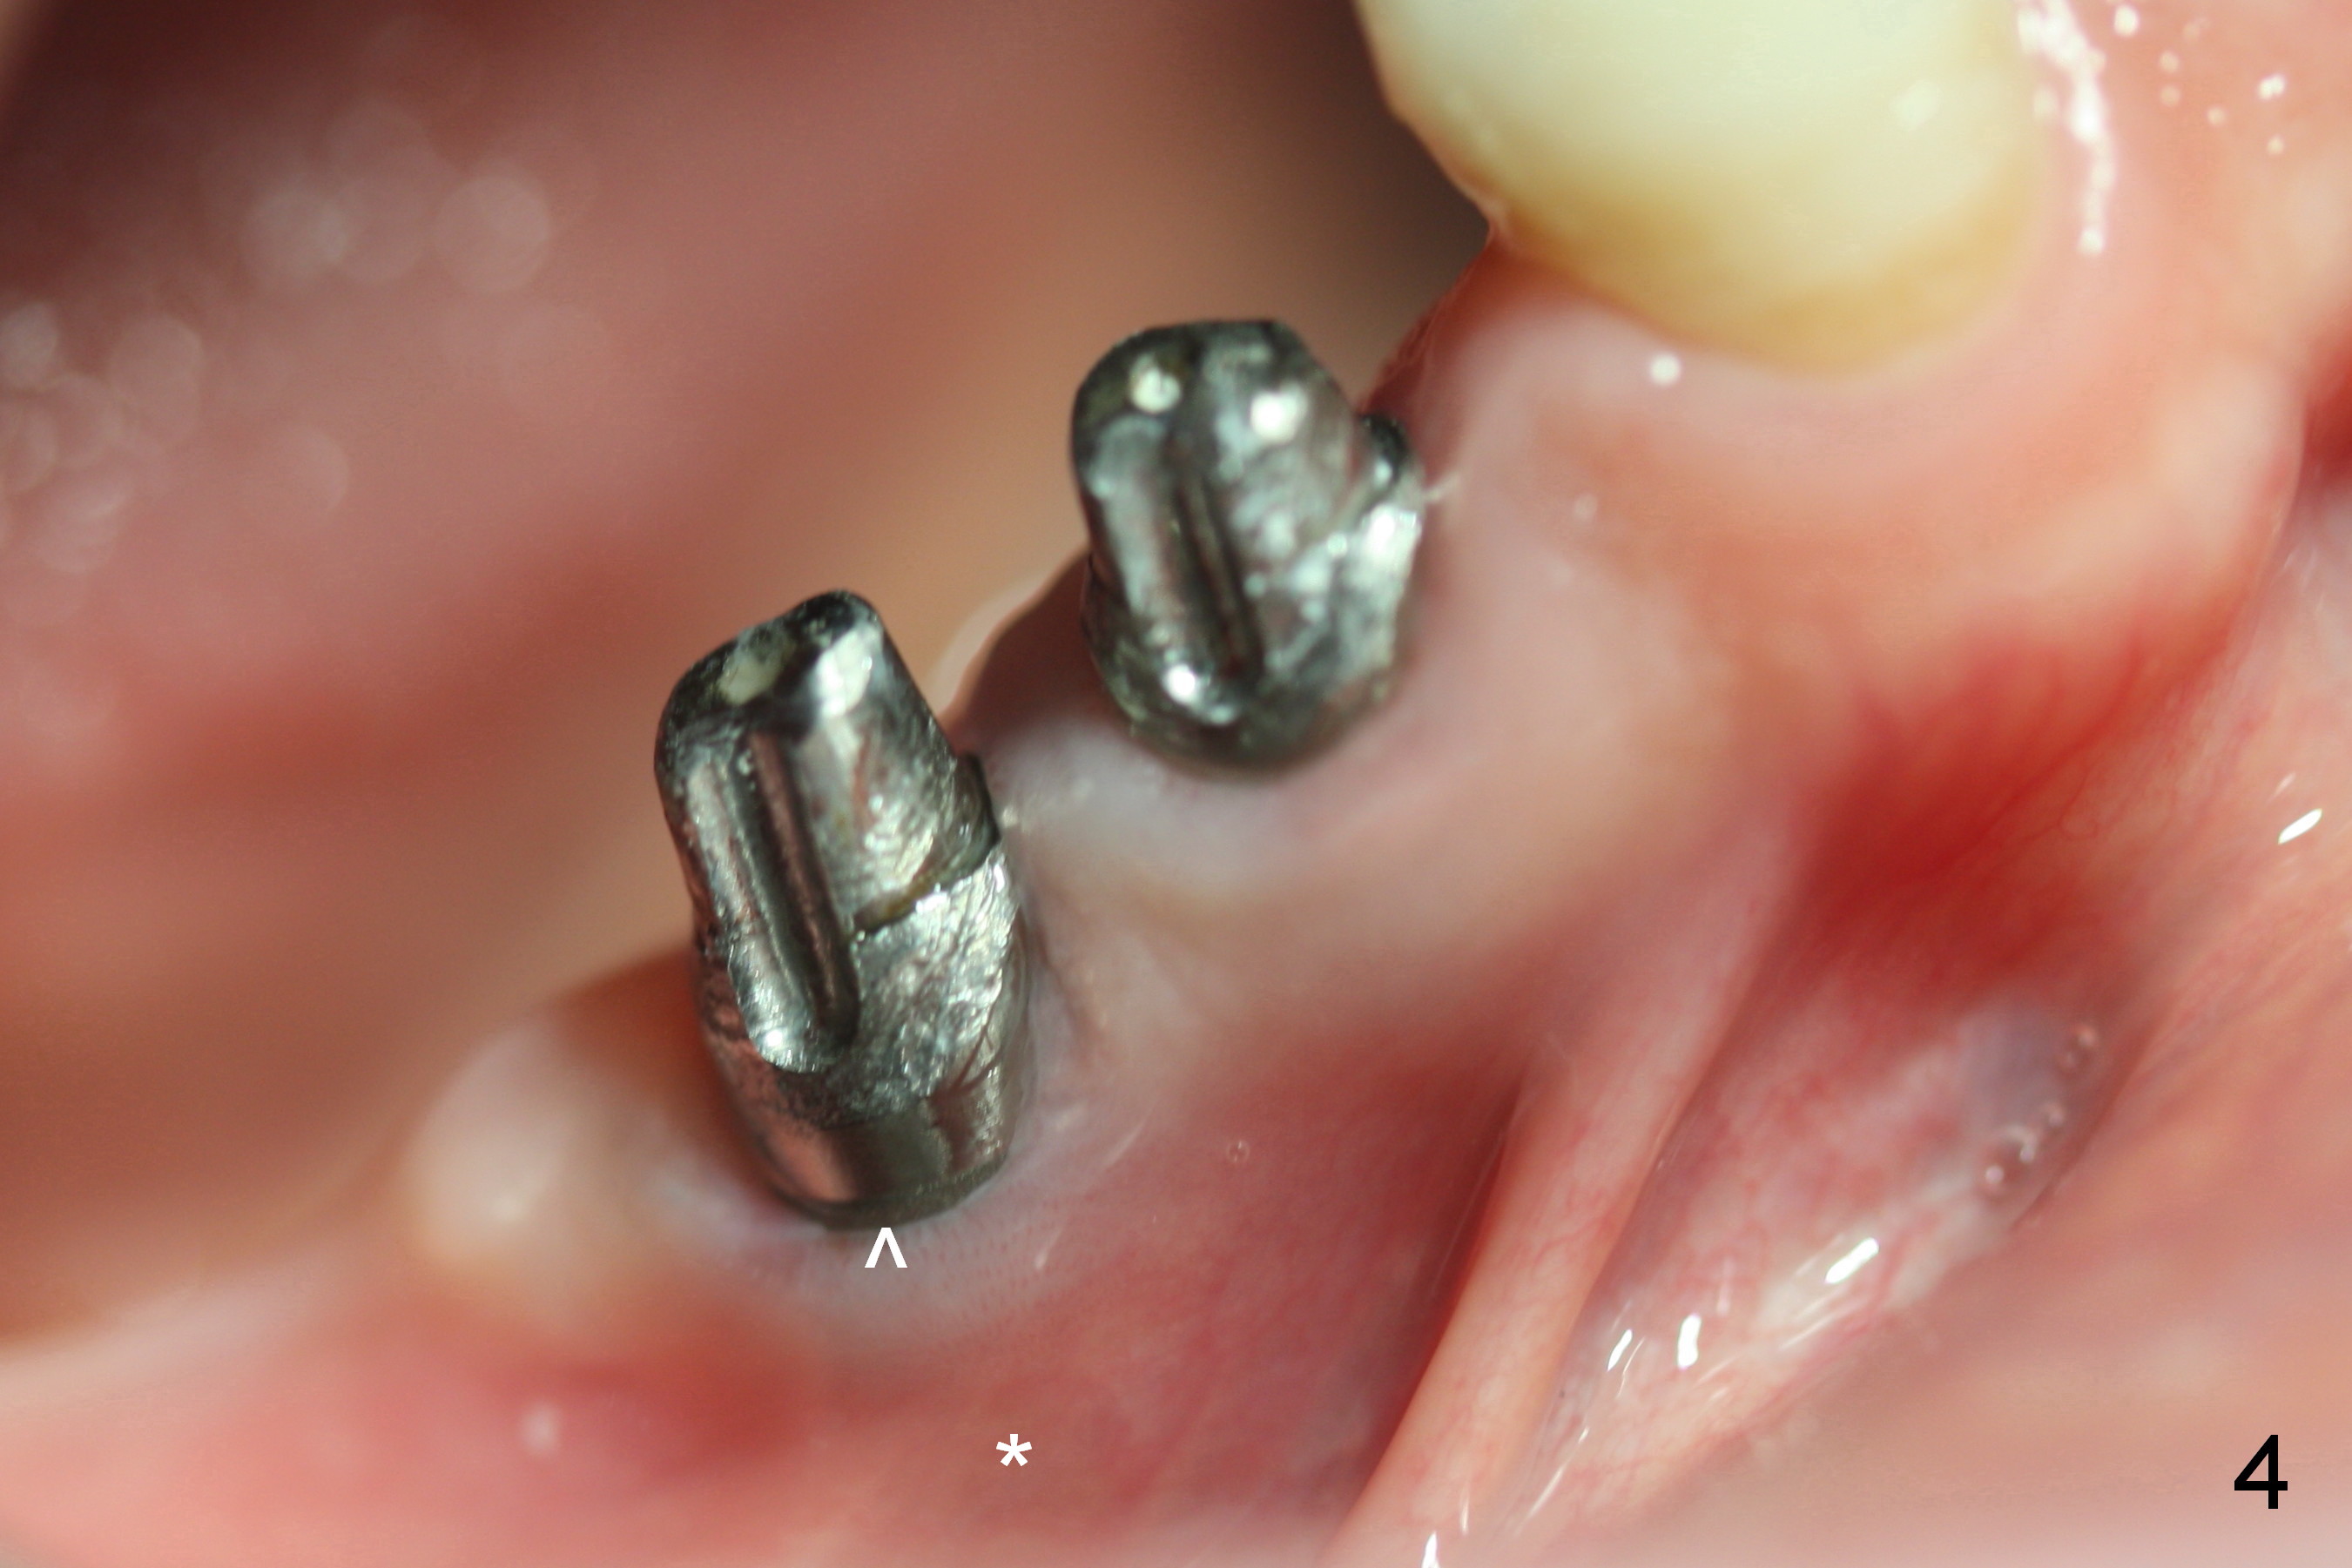

A 55-year-old lady (WJ) complains of palpation pain in the buccal vestibule over #29 implant, 5 months postop (immediately before cementation, Fig.4 *). Is the implant placed too buccally or there is buccal plate resorption after placement?

Four months and a half, the buccal margin has to be extended (Fig.3 ^). A month later, gingival recession becomes more obvious (Fig.4 ^ with exposure of the rough surface of the implant). Occlusal view demonstrates the buccal position of the implant and abutment at #29 (Fig.5). CBCT will be taken to confirm the malpositioning. If it is confirmed, the abutment and implant will be removed and un-torqued. The lingual bone will be removed; osteotomy will be also extended apically cautiously. The same or longer implant will be placed immediately. Probably two 1 piece implants will be placed at the same time at the site of #30, since the ridge is narrow.